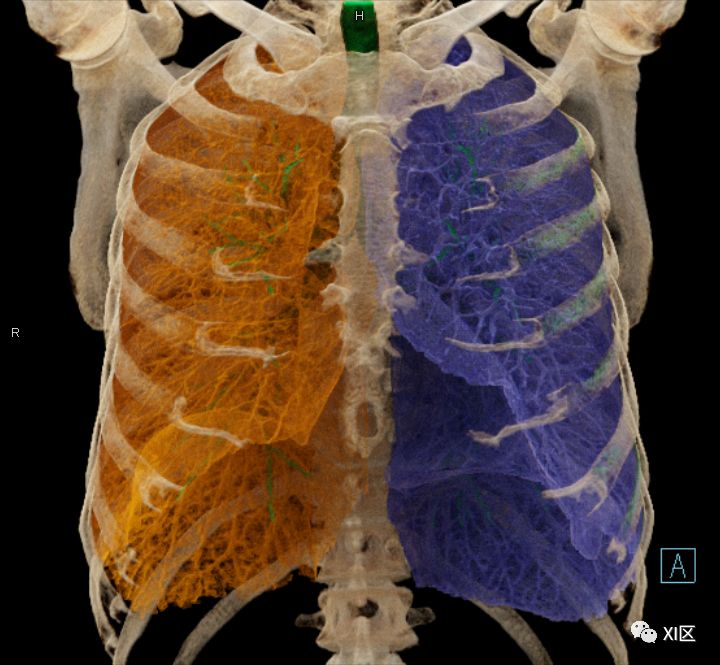

前后位,双侧位,后前位显示气道肺与胸部骨骼的关系

左肺借斜裂成上、下两叶;右肺借斜裂和水平裂成上、中和下叶三叶。